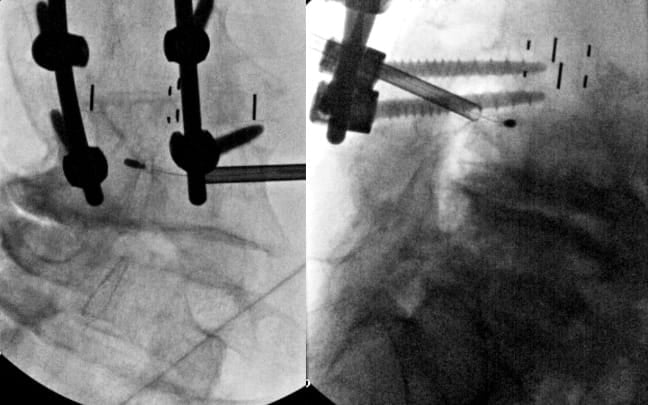

Patients with Existing Pedicle Screws

When pedicle screws occupy the standard transpedicular corridor, alternative approaches must be considered. In select cases where a CT scan demonstrates adequate space, a parapedicular approach above or below the pedicle screw can be considered while maintaining a safe distance from neural structures. This requires careful pre-procedural CT analysis to ensure a sufficient bone corridor and adequate distance from the traversing nerve root. Trajectory planning must account for the altered angles required to reach the basivertebral nerve while avoiding hardware collision. If there is inadequate space above and below the pedicle screw, an extrapedicular approach may be considered after careful examination of soft tissue and vascular anatomy (segmental artery in particular) adjacent to the pedicle root and vertebral body (Figure 6).